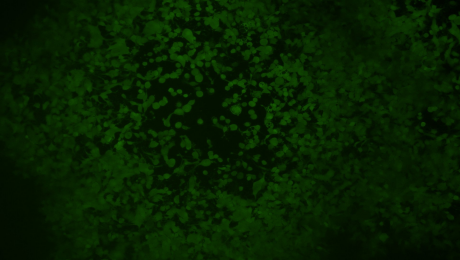

云舟生物验证扩增的VACV病毒的感染效果。VACV感染HeLa细胞后72小时拍摄。死去的细胞团块表明活病毒的存在。放大倍数:100×。左:明场。右:EGFP。